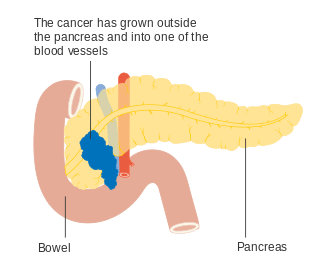

To help decide treatment, the tumors are also divided into three broader categories based on whether surgical removal seems possible: in this way, tumors are judged to be "resectable", "borderline resectable", or "unresectable".[44] When the disease is still in an early stage (AJCC-UICC stages I and II), without spread to large blood vessels or distant organs such as the liver or lungs, surgical resection of the tumor can normally be performed, if the patient is willing to undergo this major operation and is thought to be sufficiently fit.[5] The AJCC-UICC staging system allows distinction between stage III tumors that are judged to be "borderline resectable" (where surgery is technically feasible because the celiac axis and superior mesenteric artery are still free) and those that are "unresectable" (due to more locally advanced disease); in terms of the more detailed TNM classification, these two groups correspond to T3 and T4 respectively.[6]

Locally advanced adenocarcinomas have spread into neighboring organs, which may be any of the following (in roughly decreasing order of frequency): the duodenum, stomach, transverse colon, spleen, adrenal gland, or kidney. Very often they also spread to the important blood or lymphatic vessels and nerves that run close to the pancreas, making surgery far more difficult. Typical sites for metastatic spread (stage IV disease) are the liver, peritoneal cavity and lungs, all of which occur in 50% or more of fully advanced cases.[45]